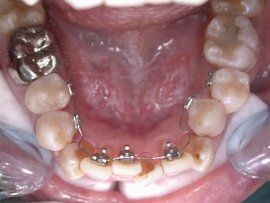

舌側隱形矯正

舌側隱形矯正技術是國際上近些年來興起的一項比較先進的正畸技術,它是將矯治器全部安裝於牙齒的舌側面進行正畸治療,外觀上看不到任何正畸痕跡。舌側矯正技術早在二十世紀七年代就開始在日本和美國出現,經過多年的理論研究和技術完善,已經自成體系,並在日本和美國廣為套用。舌側隱形矯正技術在歐美國家和日本等國家相當成熟,但是在國內舌側隱形矯正開展的卻很少,因為它對醫師操作的要求較高,技術難度較大。